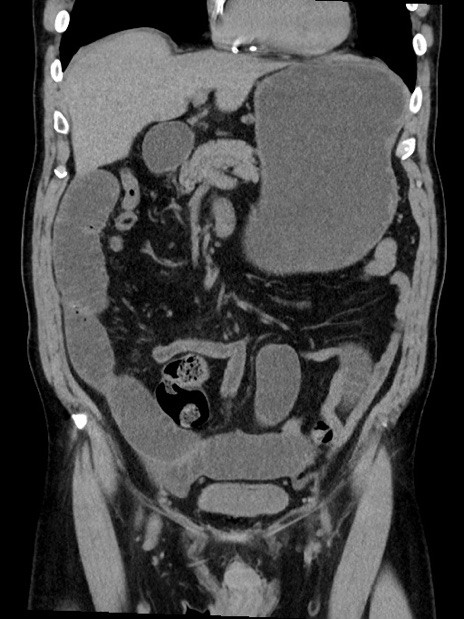

症例35(冠状断像)

【症例】70歳代 男性

【主訴】腹部膨満、嘔吐

【現病歴】昨日より腹部膨満感出現。本日増悪し、仙痛出現。嘔吐あり、受診。

【既往歴】糖尿病、胆摘後

【身体所見】BP 149/80mmHg、HR 74/min、BT 35.9℃、腹部:膨満、軟、圧痛なし。腸雑音減弱あり。上腹部正中切開瘢痕あり。

【データ】WBC 13500、CRP 1.72